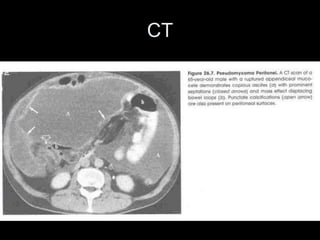

Pseudomyxoma peritonei (PMP) is a rare condition characterized by gelatinous ascites resulting from the rupture of appendiceal mucinous tumors, leading to significant abdominal complications. The incidence is approximately 2 cases per million per year, with a predominance in females, and diagnosis often relies on imaging techniques like ultrasound and CT scans. Effective treatment involves cytoreductive surgery combined with hyperthermic intraperitoneal chemotherapy (HIPEC) to manage disease progression and improve outcomes.